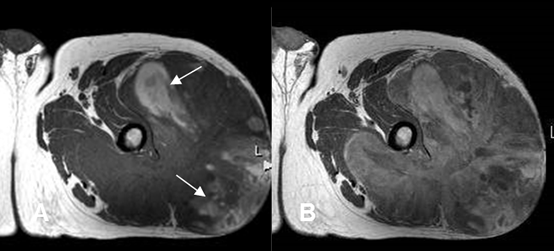

Fig 199 C. Sarcoma sinovial.

A: RM axial en T1 simple y B: RM axial en T1 con contraste. Igual paciente anterior.

Lesión de comportamiento agresivo, que cruza compartimientos. Muestra algunas áreas hiperintensas por sangrado subagudo (Flechas) y realce heterogéneo del contraste.